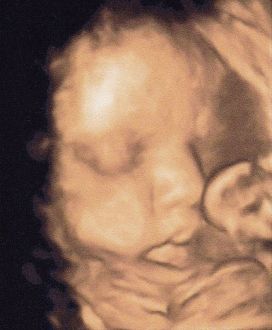

Dernière échoCette après-midi, j'avais rendez-vous pour ma dernière écho à 17H30.

Je t'avais demandé de bien enlever tes mains de devant ton visage et de nous montrer ta jolie petite bouille d'amour, ce que tu as fait pour notre plus grand bonheur...

J'étais déçue mais contente de pouvoir lui rapporter une jolie photo de toi.

Sinon, tu es un bébé parfait en pleine forme et aux mensurations parfaites.

Comme me l'avait dit l'échographiste depuis le début, tu seras un petit bébé mais avec de parfaites proportions.

Aujourd'hui, tu pèses à peu près 2 Kgs et mesures approximativement 40 cm.

L'estimation pour le jour de ta naissance si tu nés à termes est entre 2Kgs500 et 2Kgs800 et ta taille sera située entre 45 et 48 cm.

Je suis ravie de cette écho et ai adoré te voir. Je ne me lasse pas d'admirer cette photo de toi.  Message déposé le 18.05.2011 à 22:34 - Commentaires (1)